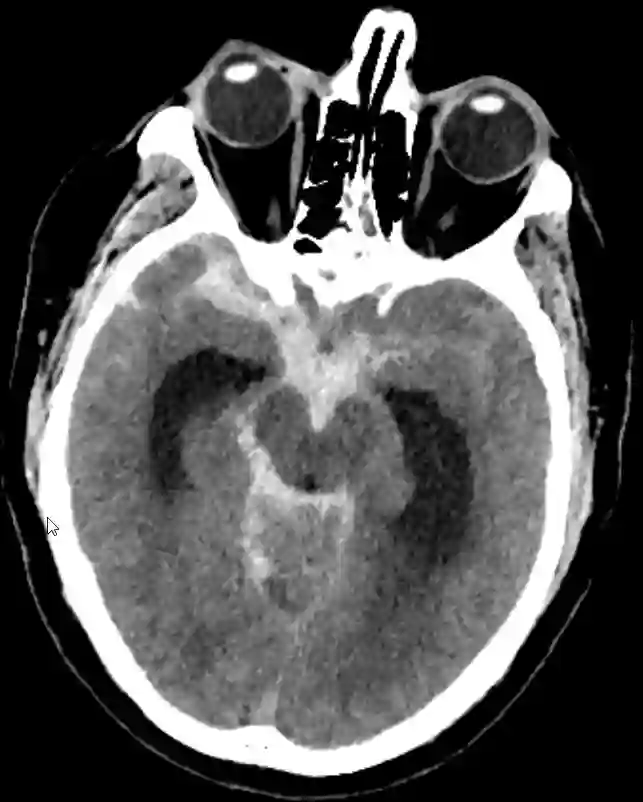

Subarachnoidalblutung mit hydrocephalem Aufstau im CT.

Ausgeprägte Subarachnoidalblutung im CT mit hydrocephalem Aufstau.

Subarachnoidalblutung CT

Axiales CT Bild eines Patienten mit einer ausgeprägten Subarachnoidalblutung und einem bereits vorhandenem Liquoraufstau.